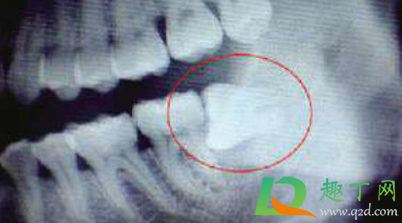

这种情况拔牙的确难度会比较大,但是拔智齿本身不是什么大手术,所以是不会有什么风险的,往专业医院拔除就可以了。横着长的智齿,牙冠和牙根水平会顶到前面牙齿上,时间久了可以造成前面磨牙牙根的吸收和含牙囊肿,所以,都建议预防性拔除。但水平阻生智齿拔除难度大,可能会造成感染干槽症,出血,下牙槽神经损伤,甚至下颌骨骨折,所以必须到专业口腔外科进行拔除,把风险降低到最低。